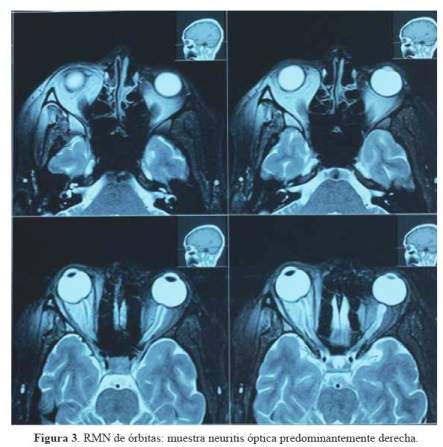

Un mes antes del ingreso, persistía con cefalea y se añadió visión borrosa. Acudió a nuestro hospital, siendo hospitalizada y evaluada por el servicio de oftalmología, quienes encontraron en el fondo de ojo, vasculitis retiniana bilateral. Se le realizó una punción lumbar, siendo la presión de apertura de 35 cm de agua y citoquímico normal. Se le realizó una nueva resonancia magnética de encéfalo, médula espinal y órbitas (figura 1, figura 2 y figura 3), que reveló neuritis óptica derecha sin lesiones en sustancia blanca; además, se repitieron determinaciones de ANA, ANCA y perfil SAF, siendo otra vez negativos. Recibió cinco pulsos de metilprednisolona, presentando mejoría parcial, quedando como secuela disminución de la agudeza visual derecha. Fue dada de alta con seguimiento ambulatorio por neurología.

En ese momento se realizó una resonancia magnética nuclear encefálica que verbalmente fue reportada por la paciente con hallazgos de neuritis óptica bilateral a predominio derecho. Se le solicitaron anticuerpos antinucleares (ANA), anticuerpos anti citoplasma de neutrófilos (ANCA), perfil de síndrome antifosfolípido (SAF), VIH, VDRL y BK de esputo, siendo todos negativos. También le realizaron potenciales evocados visuales que fueron referidos como anormales, por la paciente. Recibió cinco pulsos de metilprednisolona y continuó con prednisona 50 mg como mantenimiento, con retiro progresivo durante dos meses aproximadamente, recuperando totalmente la visión y se reincorporó a sus actividades habituales.